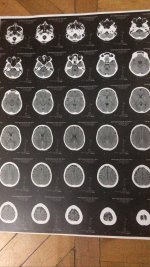

انا عندي دوخه جامده جداً وبتزيد مع اي مجهود اعمله حتى لو بسيط جدا وفي الم بسيط جداً خلف الأذنين

بقيس الضغط كويس وعملت تحليل انيميا مفيهوش حاجه ورحت دكتور انف واذن مفيش حاجه والغده مفيهاش حاجه

حقيقي انا مش عارفة اعمل ايه انا تعبت وحياتي شبه واقفه بسبب الموضوع ده